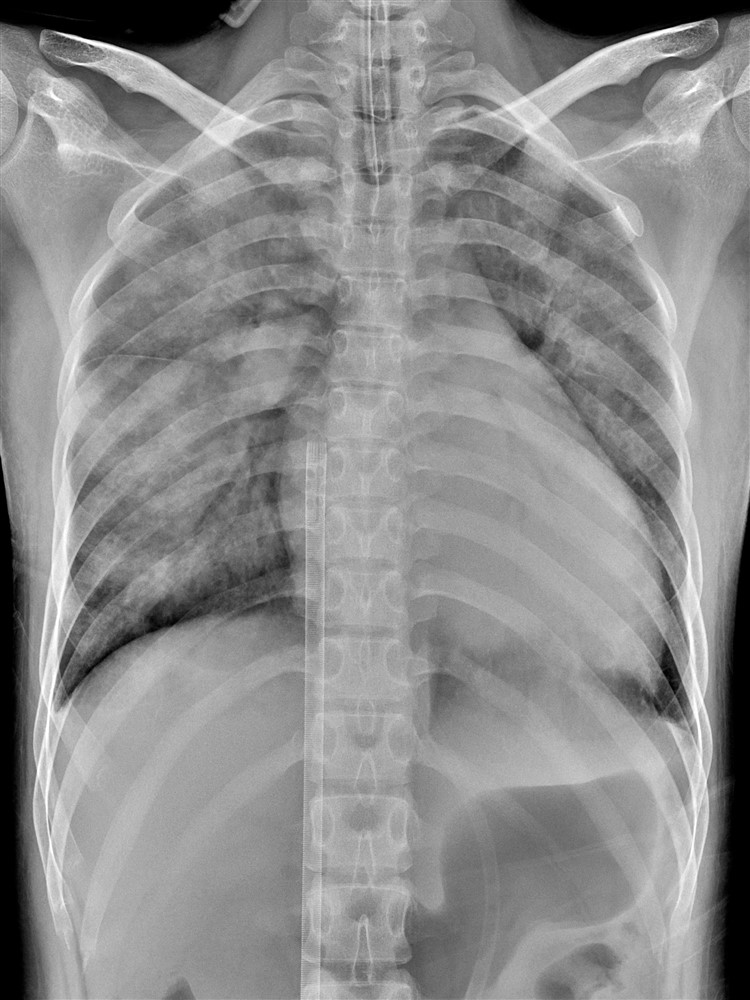

鄭小姐裝上葉克膜六小時,胸腔X 光影像中肺部幾乎呈白色,肺水腫嚴重且心臟明顯擴大。

鄭小姐住院治療一週後,心臟功能仍無明顯進步,尤其收縮功能持續偏低,正常應高於百分之五十五的左心室射出分率(Left ventricular ejection fraction, LVEF)始終低於四十五,至住院第九日晚間突發心律不整,所幸經搶救後恢復心跳,體外循環小組也立刻為她裝上葉克膜,以輔助心肺功能穩定。

外科部主任暨心臟外科醫師張睿智指出,葉克膜雖然能維持病人全身器官的正常運作,為醫療團隊爭取時間挽救性命,卻會對心臟造成極大的阻抗和壓力,使左心室無法把在肺部交換氧氣的血液打出去,全積在肺裡。若心臟功能太差的病人無法承受葉克膜造成的阻力,可能會產生肺水腫,因此需要盡快把葉克膜轉為左心室輔助器(left ventricular assist device, LVAD),幫助減壓,心臟才有機會獲得修復。